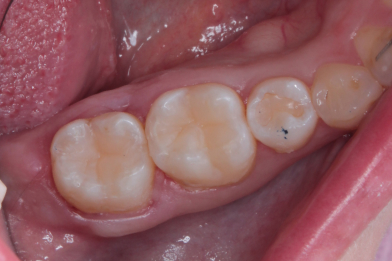

Лечение кариеса на зубах 47,46.

Колиш Максим Петрович -